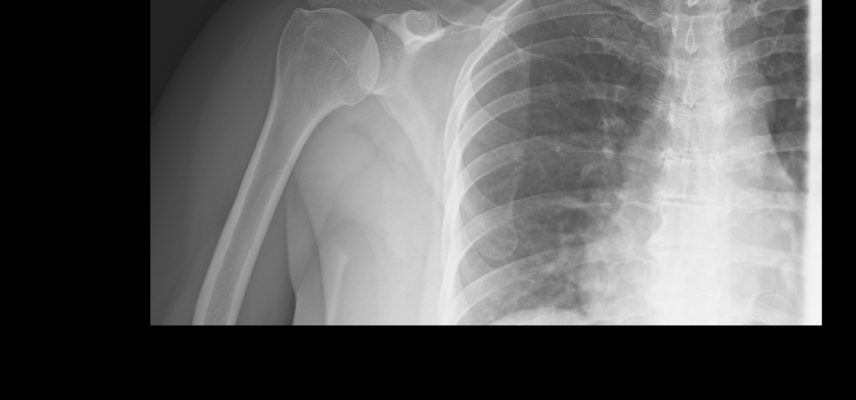

Zamrożony bark to ograniczenie ruchu

Masz problem z ograniczeniem ruchu ? A może sięgnięciem do kieszeni lub zapięciem biustonosza? czyli poprostu z ograniczeniem ruchu w barku – ramieniu. Co więcej, ból barku może nasilać się w nocy, uniemożliwiając spokojny sen. Jeśli tak, bardzo możliwe, że cierpisz na tzw. zamrożony bark (ang. frozen shoulder, medycznie: adhesive capsulitis).

To stan zapalny obejmujący torebkę stawową barku, który prowadzi do stopniowego pogorszenia ruchomości, a w konsekwencji do całkowitej sztywności barku. W rezultacie nawet najprostsze ruchy mogą stać się problematyczne.